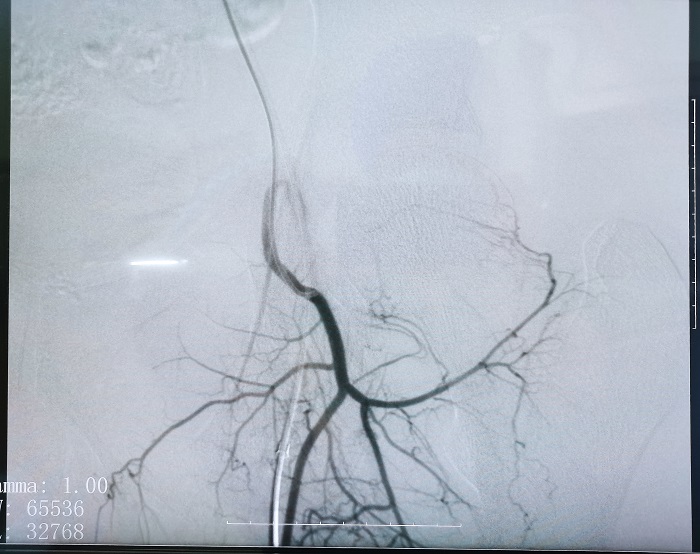

普愛平板介入中C在FTE手術過程中拍攝的造影圖像

若根據HSG的診斷,患者存在輸卵管積水,則可行輸卵管栓塞術(Fallopian tube embolization, FTE),通過介入手段,注入栓塞劑或使用彈簧圈等器材進行栓塞,可以有效地阻斷輸卵管內的血流和組織,從而治療輸卵管積水。這個過程通常是在X線或超聲引導下進行的,可以清楚地看到輸卵管的情況。